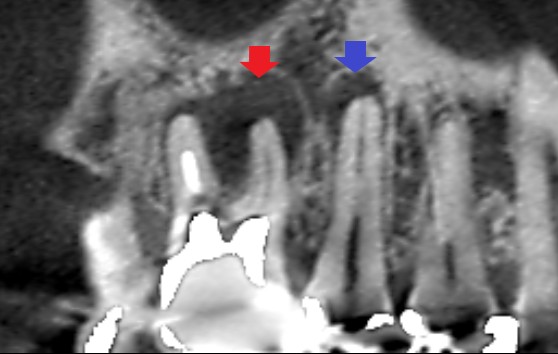

矢印の先に影がみられます。赤い矢印の先にある影は、第一大臼歯の根の先にできている膿です。青い矢印の先にある影は、第二小臼歯にできていたむし歯の影響で、歯髄の炎症が根の外まで波及して歯槽骨の吸収が起こっていることが考えられました。

第一大臼歯の精密再根管治療と第二小臼歯の精密むし歯治療1年後の矢状断のCT画像です。赤い矢印の先に見えていた第一大臼歯の膿の影が消えています。また、青い矢印の先に見えていた第二小臼歯の根の先の影も消えています。